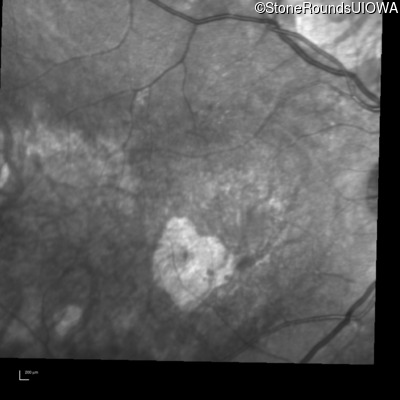

Optical Coherence Tomography - Right - 20/100

Exemplar / OCT Stack

Infrared Fundus Photograph - Right - 20/100

Exemplar